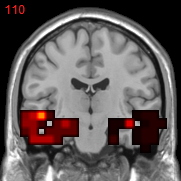

Usually, the first step of voxel-based neuroimage analysis requires preprocessing the T1-weighted image, such as segmentation and registration of grey matter (GM), white matter (WM) and cerebral spinal fluid (CSF). However, some systematic biases due to scanner difference and different population etc., can be introduced in this pipeline [2]. Part of them can be helpful to the discrimination of subjects from normal controls (NC), but may not be directly related to the disease. For example in structural Magnetic Resonance Imaging (sMRI) images of subjects with Alzheimer’s Disease (AD), after spatial normalization during simultaneous registration of GM, WM and CSF, the GM voxels surrounding lateral ventricle and subarachnoid space etc. may be mistakenly enlarged caused by the enlargement of CSF space in those locations [2] compared to normal template, as shown in Fig. 1. Although these voxels/features are highly correlated with disease, they can’t be regarded as lesion features in an interpretable model. In this paper we refer to them as “Procedural Bias”, which should be identified but is neglected in the literature. We observe that it can be harnessed in our voxel-based image analysis to improve the prediction of disease.

Figure 1: The overlapped voxels among top 150 negative value voxels in each fold of βpresubscript𝛽𝑝𝑟𝑒\beta_{pre} at the time corresponding to the best average prediction result in the path of GSplit LBI using 10-fold cross-validation. For subjects with AD, they represent enlarged GM voxels surrounding lateral ventricle, subarachnoid space, edge of gyrus, etc.

The process of feature selection combined with prediction accuracy can be analyzed together along the path. The result of 30ADNC is used as an illustration in Fig. 3. We can see that βpresubscript𝛽𝑝𝑟𝑒\beta_{pre} (blue curve) outperforms βlessubscript𝛽𝑙𝑒𝑠\beta_{les} (red curve) in the whole path for additional procedural bias captured by βpresubscript𝛽𝑝𝑟𝑒\beta_{pre}. Specifically, at βpresubscript𝛽𝑝𝑟𝑒\beta_{pre}’s highest accuracy (t5subscript𝑡5t_{5}), there is a more than 8%percent88\% increase in prediction accuracy by βpresubscript𝛽𝑝𝑟𝑒\beta_{pre}. Early stopping regularization at t5subscript𝑡5t_{5} is desired, as βpresubscript𝛽𝑝𝑟𝑒\beta_{pre} converges to βlessubscript𝛽𝑙𝑒𝑠\beta_{les} in prediction accuracy with overfitting when t𝑡t grows. Recall that positive (negative) features represent degenerate (enlarged) voxels. In each fold of βpresubscript𝛽𝑝𝑟𝑒\beta_{pre} at t5subscript𝑡5t_{5}, the commonly selected voxels among top 150 negative (enlargement) voxels are identified as procedural bias shown in Fig. 1, where most of these GM voxels are enlarged and located near lateral ventricle or subarachnoid space etc., possibly due to enlargement of CSF space in those locations that are different from the lesion features.